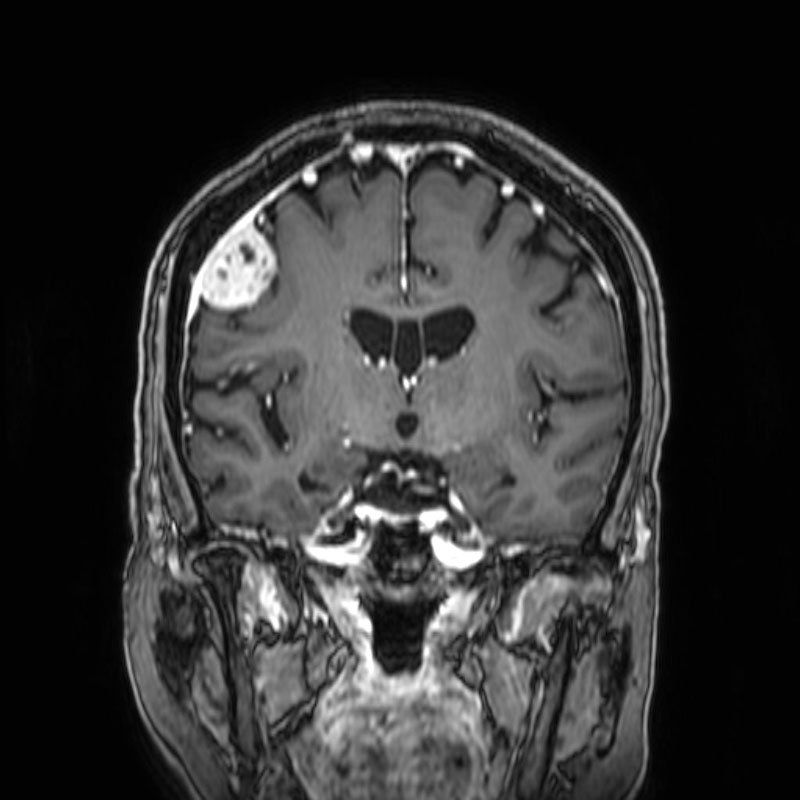

No.’25_108 手術前1

No.’25_108 手術前2

右頭頂葉腫瘍

頭蓋内腫瘍摘出術